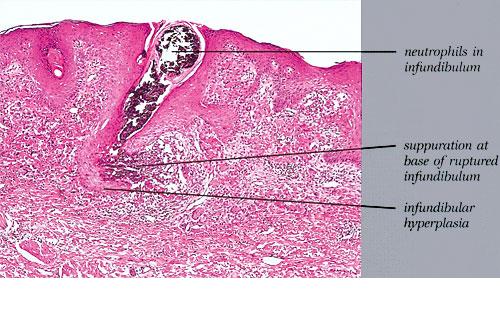

Elastosis perforans serpiginosa = المران الثاقب الزاحف